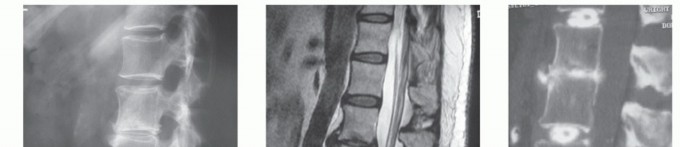

Lateral radiographs allow for measurement of the intervertebral disc height and allow comparison to other lumbar intervertebral discs (FIG 2A).

MRI provides excellent visualization of the discs, the degree to which they have degenerated, and the relationship of the discs to the adjacent endplate and surrounding neurologic structures (FIG 2B).

Computed tomography (CT) discography provides more detailed information about the disc morphology after contrast administration (FIG 2C).

FIG 2 • A. Lateral radiograph showing DDD at the L2-L3 level. B. Sagittal T2-weighted MRI of the same patient with low signal intensity in the nucleus of the L2-L3 disc. Anterior and posterior disc bulges are present. C. Sagittal CT discogram of the same patient showing dramatic loss of integrity of the L2-L3 nucleus and annulus with leakage of contrast anteriorly. The patient's pain was concordant at the L2-L3 disc level. The L1-L2 and L3-L4 discs served as negative controls with regard to both disc architecture and pain.*